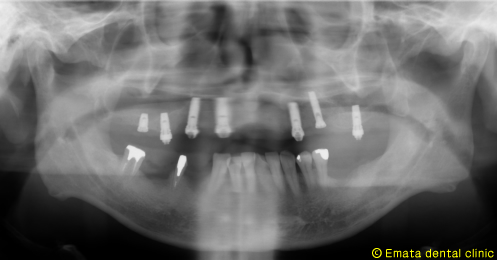

| All-on-4は4本ではないかとおもいますが、骨の状態や対合歯が自分の歯なのでより確実性をもたせたいため5本で立ち上げ、2本はスリープさせました。

この症例のポイントは、ソケットリフト部位への即時負荷でしょう。アダプテーションテクニックにより40ニュートンの初期固定がえられました(専門的になってしまいましたね)。 麻酔専門医の先生が静脈内鎮静法を行っていますので患者さんは半分寝ているうちに手術が終わってしまいます。 |

仮歯までいれるのに半日かかりましたが、患者様には大変喜んでいただきました。 |